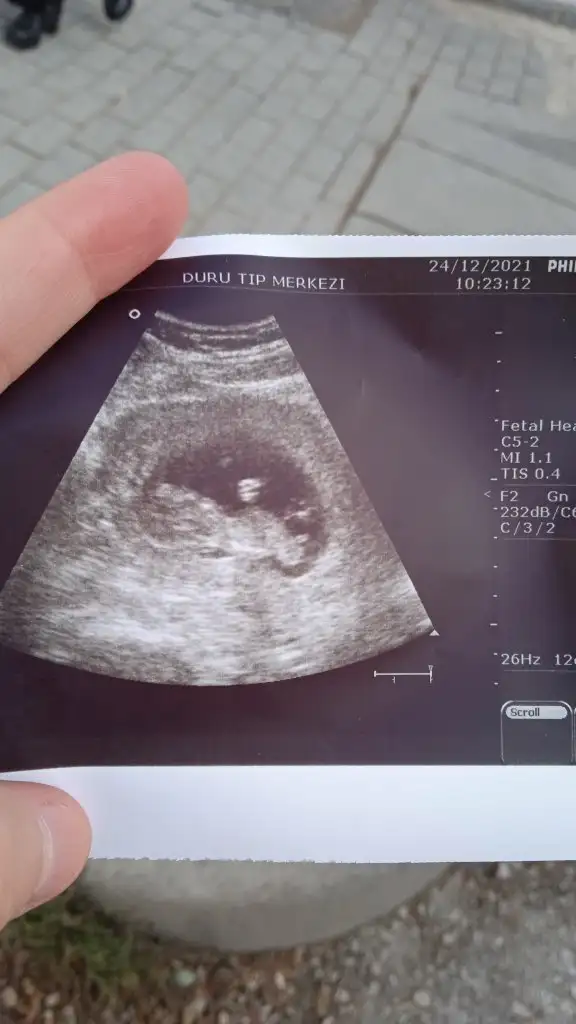

kesen maşallah yuvarlak kız gibi duruyormuş ama paşa benceKiz dedin cnm 16 haftalık oldu ama daha belli degil atiyim yıne ben eski ultrasonu

prenses gibiBu da bi arkadaşımın bebegi 12 hastalıkmış karindan

11 hafta 1 günlük karından bu da arkadaşımın yorumlarsanız sevinirim :)Selam Kızlarbir çok kişi gruplardan beni bilir. Yine yetiştim imdatlara

Çoook uzun bir süre araştırma okuma yaptıktan sonra sizlere bu başlığı açtım çevremde tüm gebelere de denedim. Bunun sırrını çözen İnstagramda (isim vermeyim) işi ticarete dökmüş bile.Nub, Ramzi,Çin Rus Japon Takvimleri, Yüzük Yöntemi bir çok şey size sayabilirim.

5 ve 14. haftaya kadar olan ultrason fotolarınızı paylaşın. Vajinadan mı yoksa karından mı çekildiğini ve kaç haftalık olduğunu da mutlaka belirtin.